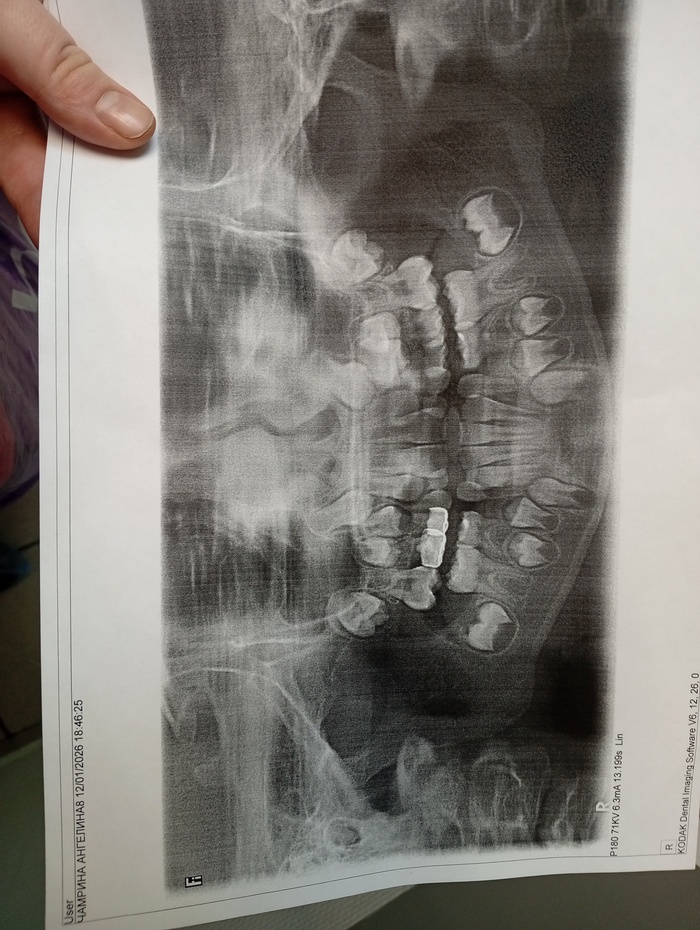

У моей дочери 7 лет начали появляться постоянные зубы и явно видно, что челюсть мала для таких больших зубов.

Прикреаиоа фото зубов и рентген от января. Внизу 2 зуба удаляли.